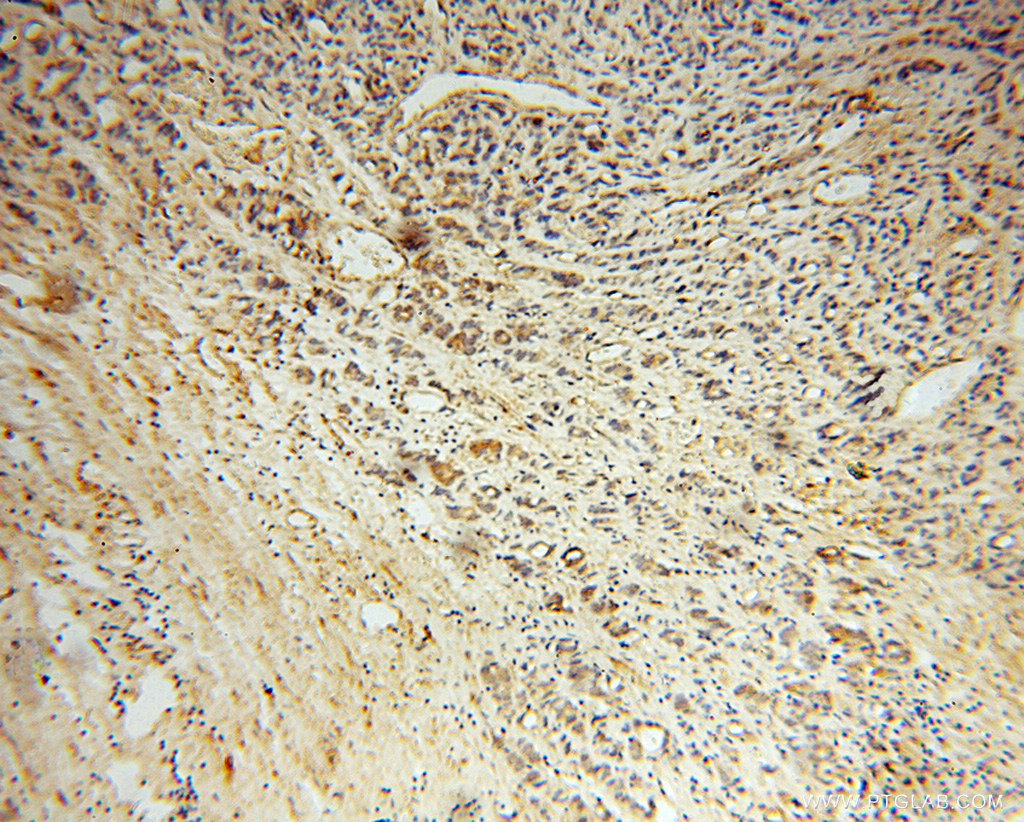

Supportive validation

- Submitted by

- Proteintech Group (provider)

- Main image

- Experimental details

- Immunohistochemical of paraffin-embedded human gliomas using 14772-1-AP(NOG antibody) at dilution of 1:50 (under 10x lens)

- Sample type

- tissue